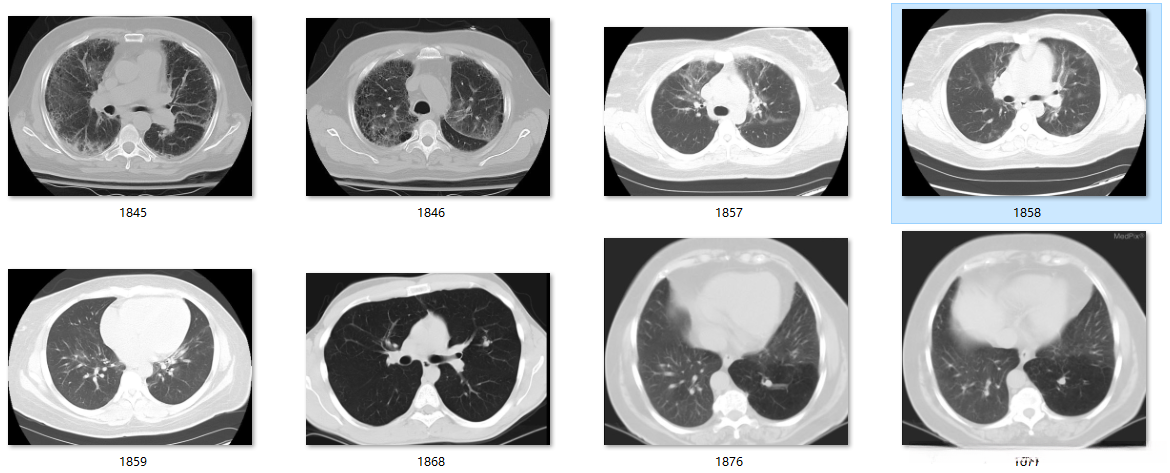

输入:

输出: